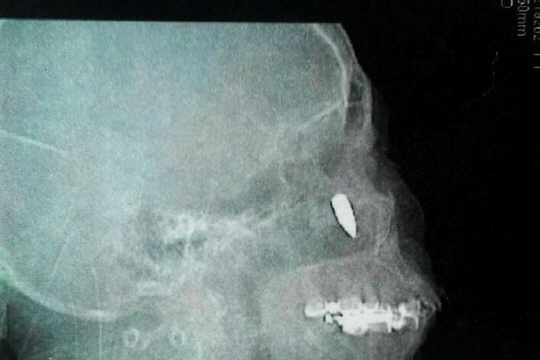

차이나타임즈의 최근 보도에 따르면 중국 랴오닝성에 거주하는 차오(62)라는 여성이 병원 검진 결과 코 안쪽에 있던 길이 2.5cm의 총알을 발견했다.

놀라운 것은 이 여성은 48년 동안 이런 사실을 몰랐다는 것. 그녀는 만성적인 코막힘, 두통, 림프절이 붓는 증세를 갖고 생활하다가 최근 통증이 악화되자 병원을 찾았다.

의료진은 여성의 코 안쪽 부분을 절개해 총알을 제거하는 수술을 했다.

이 여성은 "14살때 오른쪽 관자놀이가 따끔한 적이 있었다"며 "그냥 작은 돌멩이에 맞은 줄 알았다"고 밝혔다.

현지 언론은 당시 이 여성이 어디선가 날아온 유탄에 맞은 것으로 추측했다.